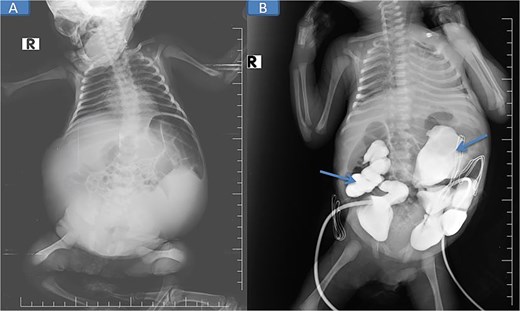

On examination, the neonate weighed 2.905 kg, measured 45 cm in length, and had a head circumference of 32 cm, all appropriate for gestational age. He was lethargic, in respiratory distress requiring continuous positive airway pressure (CPAP) oxygen support, and had a soft, distended, prune-like abdomen (Fig. 1). The anal canal was patent, and stool passage was normal. Both scrotal sacs were empty.

Pre-nephrostomy drainage abdominal distention (A) and post-nephrostomy (B).

Pre-op abdominal X-ray (A) and post-operative percutaneous nephrostomy procedure with contrast injection through the nephrostomy (B).

The patient was stabilized with CPAP oxygen, intravenous antibiotics (ampicillin, cefotaxime, metronidazole), and supportive care. Following preoperative evaluation and parental consent, bilateral nephrostomy was performed, yielding significant urine drainage. Postoperatively, renal function improved with normalization of creatinine and urea, and by Day 5 post-nephrostomy, values had returned to normal (urea 13 mg/dl [reference: 10–45] and creatinine 0.48 mg/dl [reference: 0.35–1.10]), accompanied by a reduction in abdominal distention.